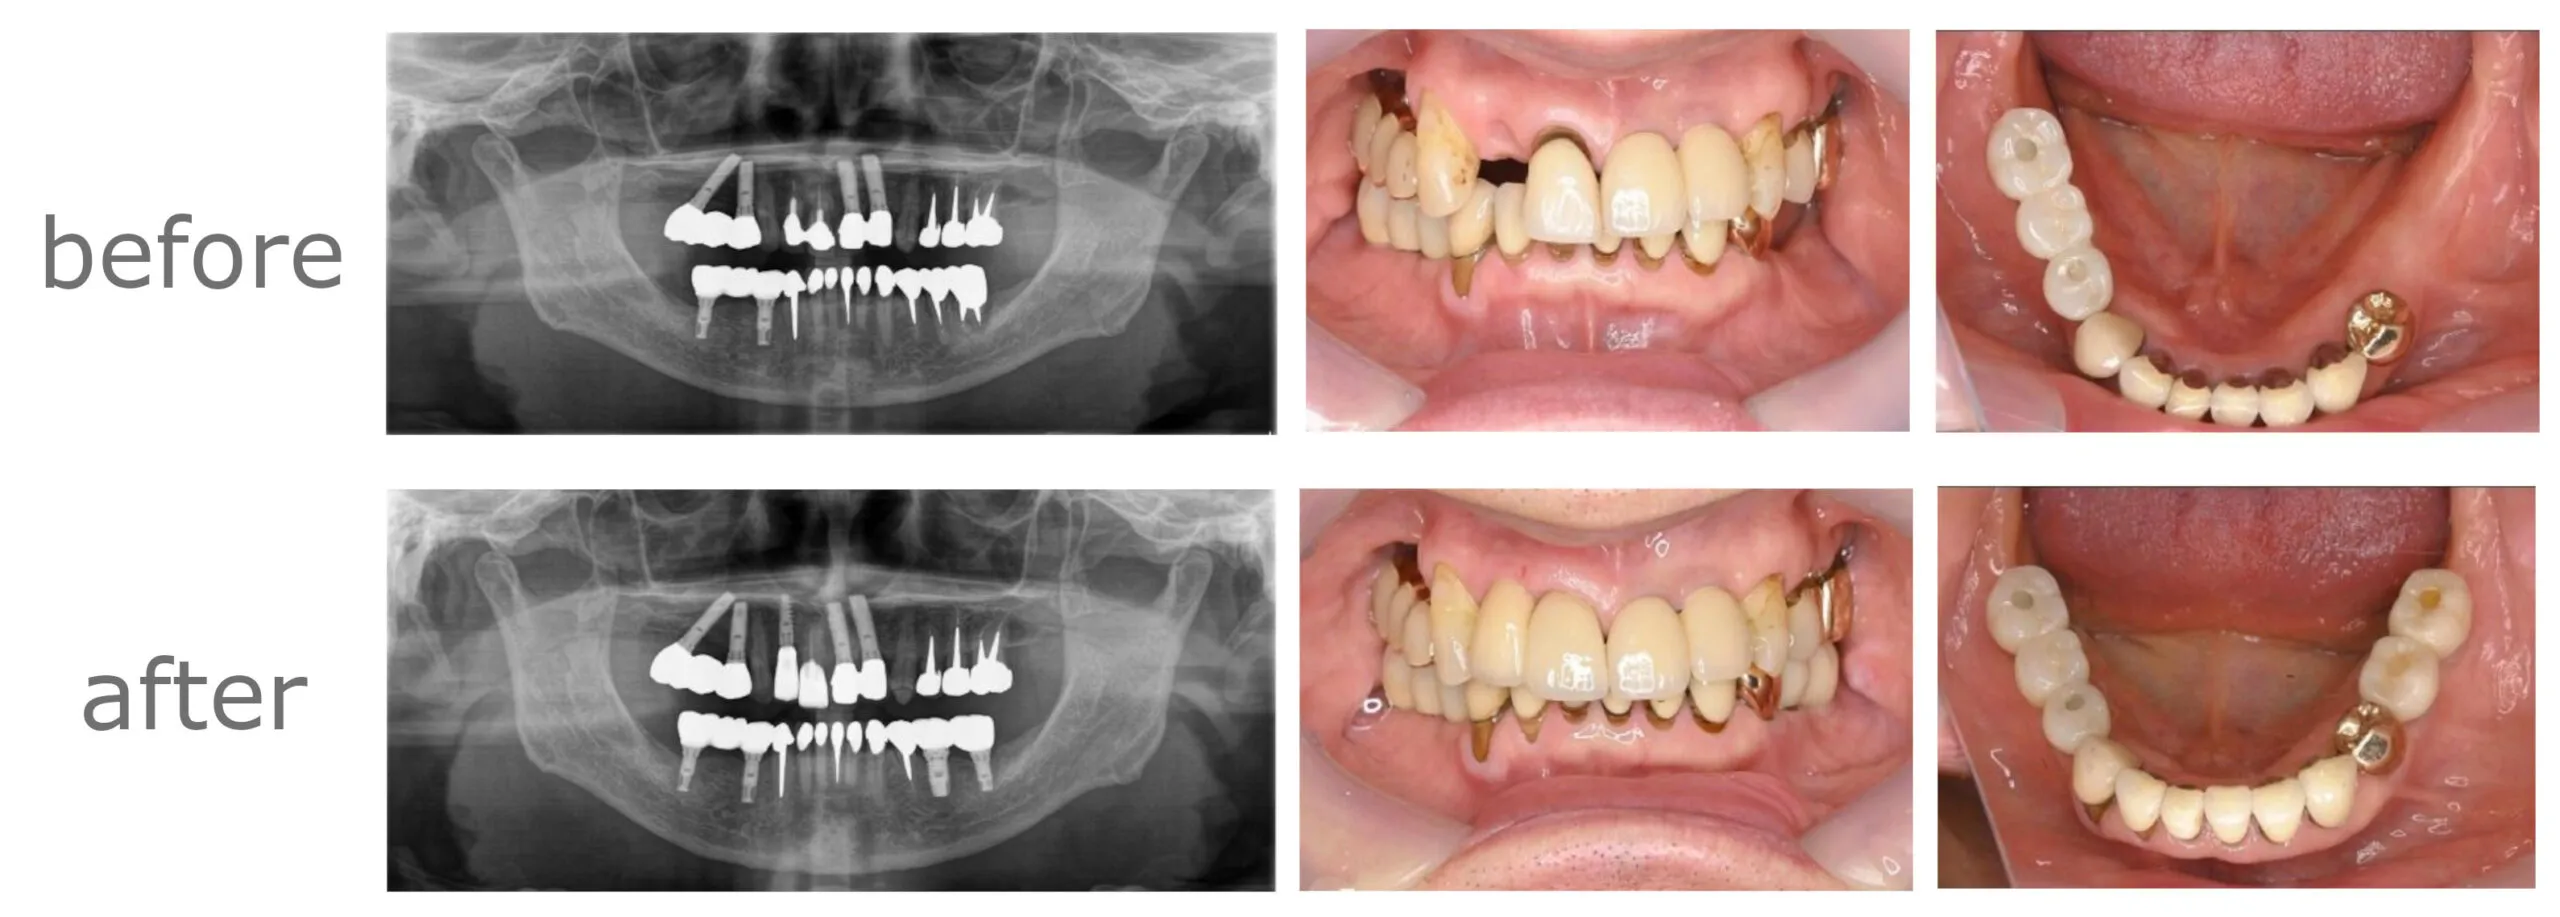

【年齢・性別】

60代・男性

【主訴】

左下の奥歯と右上の前歯が噛むといたい

【期間】

10ヶ月

【通院回数】

20回

【費用】

1,848,000円